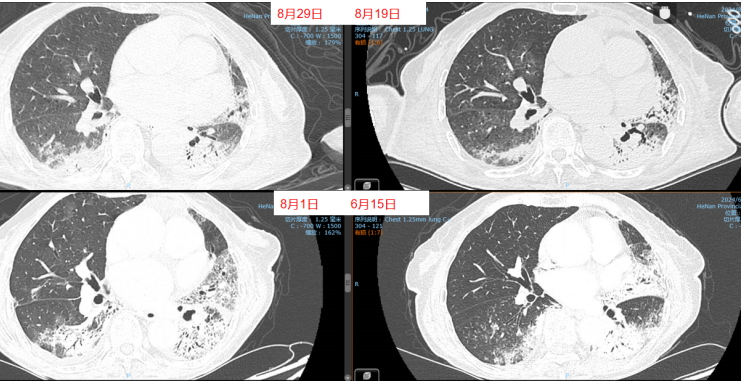

- 胸部CT(2024-06-13):左肺舌段和左下叶斑片实变影,右肺下叶可见斑片状阴影,肺中叶散在病变(图1)。

经过上述治疗,患者WBC、CRP、LDH、PCT均逐渐下降,肌酐正常。8月10日检查:WBC 9.1×109/L,CRP 6.8 mg/L,PCT 0.04 ng/ml,LDH 406 U/L。8月3-10日期间,患者心率持续变快,需要两种血管活性药物控制血压,无法进行俯卧位通气。ECMO上机前,患者右肺渗出性病变明显加重(图3)。

8月11日呼吸机吸氧浓度40%,ECMO气浓度约为80%,持续3天,激素减量氧合恶化,因心脏问题不能俯卧位通气(心率快,应用艾司洛尔及胺碘酮控制心室率)。气道分泌物不多,炎症指标正常。心脏问题,快速性心律失常,请心内科专家会诊,考虑舒张功能障碍,建议盐酸地尔硫卓联合胺碘酮控制心室率,血压低考虑可能血管张力问题,为减轻去甲肾上腺素对心脏的刺激,调整间羟胺维持血压。6月26日用抗肿瘤靶向药物后,8月1日肺部CT,双肺病变明显加重,肿瘤进展还是感染诱发?或是肿瘤靶向药物引起的免疫相关性肺损伤?下一步怎么办?肿瘤靶向药物还能用吗?8月11日请詹庆元教授会诊,考虑肿瘤靶向药物引起间质性肺炎可能性大,甲强龙80 mg q12h;心内科建议倍他乐克6.25 mg q12h口服联合盐酸地尔硫卓控制心室率;间羟胺替换去甲肾上腺素。8月12日心率65~85次/分,俯卧位8小时,白天ECMO 80%下调60%。患者氧合持续好转,随着病情好转,抗生素降阶梯治疗。8月13日,BALF涂片发现大量白细胞,以及多种形态阴性杆菌,像洋葱伯克霍尔德菌和伊丽莎白菌。8月14日,tNGS结果回报按蚊伊丽莎白菌、洋葱伯克霍尔德菌和脓肿分枝杆菌。据此调整抗感染药物:磺胺2片tid,多黏菌素E,美罗培南,利奈唑胺,伏立康唑。8月20日撤离ECMO。8月21日,病原学提示脓肿分枝杆菌进行性增多,加用左氧氟沙星。8月26-28日尝试甲强龙减量(60 mg→40 mg),患者再次再次出现氧合变化,未能成功转换为无创通气,有创通气PS降至8 cmH2O,PEEP 5 cmH2O。复查胸部CT,发现右肺渗出性病变再次出现。8月29-30日,甲强龙剂量调整为80 mg。8月31至9月3日,甲强龙剂量调整为60 mg。8月27日复测tNGS,回报木糖氧化无色杆菌(序列数47605),人类疱疹病毒1型(序列数176998),按蚊伊丽莎白菌、洋葱伯克霍尔德菌和脓肿分枝杆菌序列数较前减少。细菌室回报木糖氧化无色杆菌。患者出现了一些不良反应,包括骨髓抑制,纤维蛋白原、血小板、血红蛋白、白细胞、淋巴细胞数都在降低。考虑可能是磺胺药物和利奈唑胺引起,所以停用这两种药物。调整抗感染药物:阿米卡星雾化,左氧氟沙星,多西环素,伏立康唑,阿昔洛韦。之后由于不良反应,8月31日停用了左氧氟沙星和多西环素。9月3日查血,患者血小板升高。如下图所示,6月15日为抗肿瘤药物使用前,8月1日为抗肿瘤药物使用后,8月19日第一次复查CT,激素减量后,8月29日再次复查CT,右肺渗出性病变较前明显增多(图4)。

图4 患者影像学变化